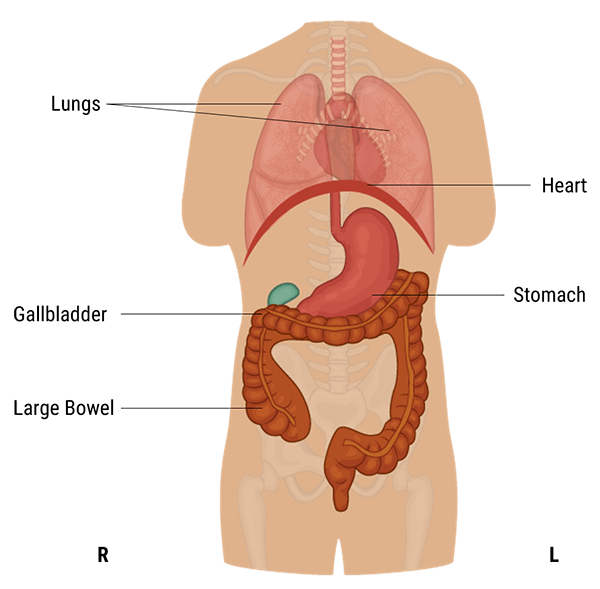

A protective layer called the peritoneum, which plays a role in supporting organs, immunity, and fat storage, lines the abdominal cavity. As shown in this diagram, there is no overlapping partition between the pelvic and abdominal cavities.

The abdominal cavity is the largest body cavity in humans, it is lined by a thin, serous membrane called the peritoneum and contains different vital organs such as the liver, gallbladder, stomach, spleen, pancreas, kidneys, ureters, intestines, and the arterial and venous systems.

The stomach is a thick-walled digestive organ found on the left side of the abdomen. It is followed by the first portion of the small intestine, called the duodenum.

The Liver is the largest organ in the abdomen. It is located on the upper right side of it, right under the diaphragm. It has two lobes that are separated by a ligament. It plays a crucial role in our bodies as it maintains normal blood glucose levels, produces bile, and detoxifies the blood.

The Gall bladder is found below the liver and is connected to it. It stores and concentrates bile that is sent to the duodenum when needed for fat digestion and absorption.

The spleen is part of the immune system. Its functions include taking part in the production of white blood cells, storing platelets, and destroying dead red blood cells and harmful substances.

The Pancreas is a part of the digestive system, it produces important digestive enzymes, as well as insulin and glucagon, which are crucial for the metabolism of carbohydrates in our bodies.

The small intestine is found between the stomach and large intestine and is made up of three parts: the duodenum, jejunum, and ileum. It is a long, tube-shaped digestive organ, where digestion and absorption of nutrients take place.

The large intestine is the organ to which undigested material is sent. It is U-shaped and is made up of the cecum, colon, rectum, canal, and appendix. Absorption of water and electrolytes and the formation of feces all occur here.

The two kidneys are found on either side of the abdomen. They play an essential role in the body, because they ensure the detoxification of the blood, the creation of urine, and the maintenance of water and acid balance in the body. Attached to each kidney are tubes, called the ureters, which connect them to the urinary bladder. In addition to the kidneys’ functions, the adrenal glands found on the kidneys produce important hormones, such as norepinephrine and ADH.

The pelvic cavity is a body cavity that is bounded by the bones of the pelvis. It contains primarily the reproductive organs, the urinary bladder, the pelvic colon, and the rectum. In the female, the uterus and vagina occupy the interval between these viscera.

As shown in this diagram, the abdominal cavity has been divided into four quadrants: the right upper quadrant, the left upper quadrant, the right lower quadrant, and the left lower quadrant. These quadrants have different abdominal and pelvic organ systems. For example, the right upper quadrant contains the liver, gallbladder, and right colic flexure, whereas the right lower quadrant contains the appendix, terminal ileum, and right ovary in females.